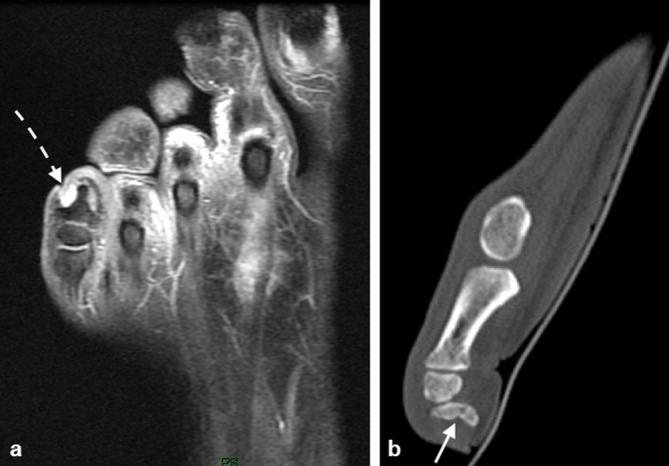

Imaging of the spectrum of bony injuries in the diabetic foot: a case series with emphasis on non-Charcot fractures.

Diabetes mellitus is associated with an increased risk of lower limb injuries. Peripheral neuropathy, often associated with diabetes, has been demonstrated to increase the risk of fracture almost two-fold and is associated with complications related to fracture healing. Detection of neuropathy-related foot injury is frequently delayed owing to the paucity of symptoms and low degree of suspicion by the clinician. Early recognition of fracture or bone injury and appropriate treatment are critical in preventing debilitating foot deformity and disability. Therefore, the astute radiologist cognizant of these potential injuries plays an essential role in early diagnosis of bony injuries in the diabetic foot. We present a series of radiological images that depict a range of osseous injuries in the diabetic foot and emphasize the role of the radiologist in early recognition of these abnormalities.

糖尿病与下肢受伤风险增加相关。外周神经病变常与糖尿病有关,已被证实会使骨折风险增加近两倍,且与骨折愈合相关的并发症有关。由于症状稀少且临床医生怀疑程度低,神经病变相关足部损伤的检测常常延迟。早期识别骨折或骨损伤并进行适当治疗对于预防使人衰弱的足部畸形和残疾至关重要。因此,敏锐地认识到这些潜在损伤的放射科医生在糖尿病足骨损伤的早期诊断中起着至关重要的作用。我们展示了一系列放射影像,这些影像描绘了糖尿病足中的一系列骨损伤,并强调了放射科医生在早期识别这些异常情况中的作用。